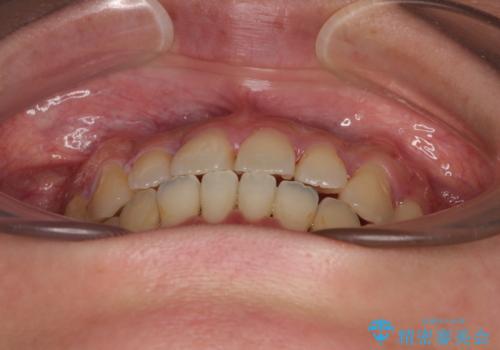

- 上下前歯のデコボコやクロスバイトを気にして来院された患者様です。

上顎歯列が下顎の歯列に対して狭小であり、一部下顎の奥歯が上顎よりも外側に位置している状態でした。

上顎の急速拡大装置を使用して上顎骨を側方に拡大することで上顎歯列を拡大し、下顎歯列も拡大できるようにすることで、歯列を整えることとしました。

歯列矯正では基本的に骨格を改善することはできませんが、急速拡大装置(MARPE)を使用することで上顎骨を側方に拡大させることができ、咬合状態を大きく改善することができます。